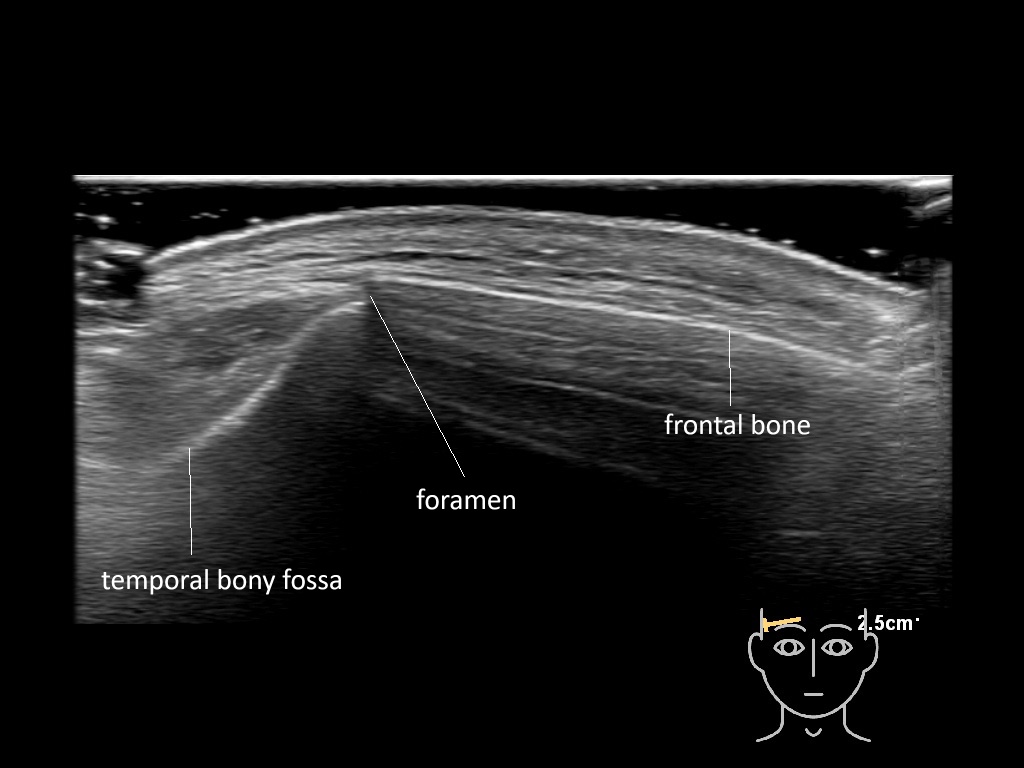

In this section you will learn more about the different layers of the face with the use of ultrasound. When you click on the secondary ultrasound image, you will see the different structures as an overlay. This will help to train yourself to recognize the different layers of the face.

Study the first image to recognize the different layers. If you are sure about the layers, swipe to the second image to view the answer (if applicable).